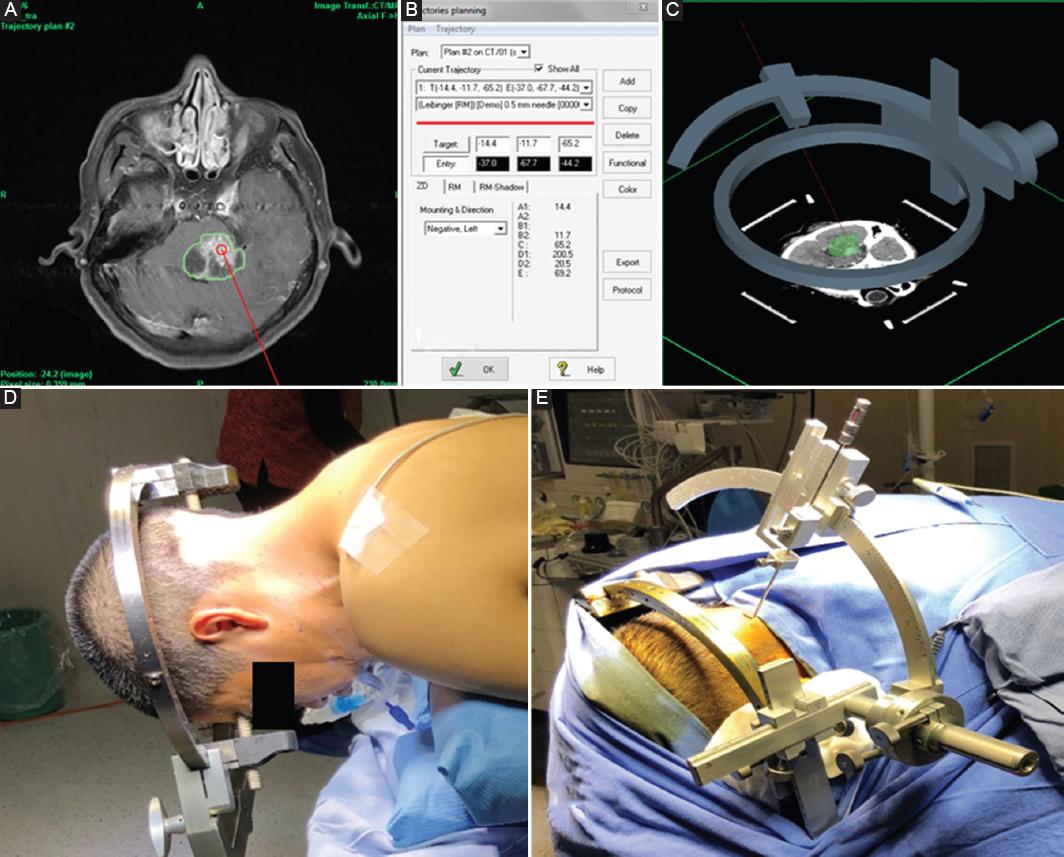

Mechanisms of Nerve Damage in Neuropathies Associated with